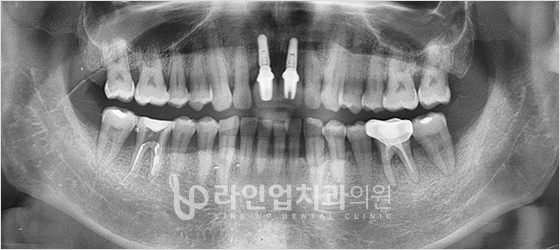

Имплант хийлгэхийн өмнө ба дараах зураг

Before

After